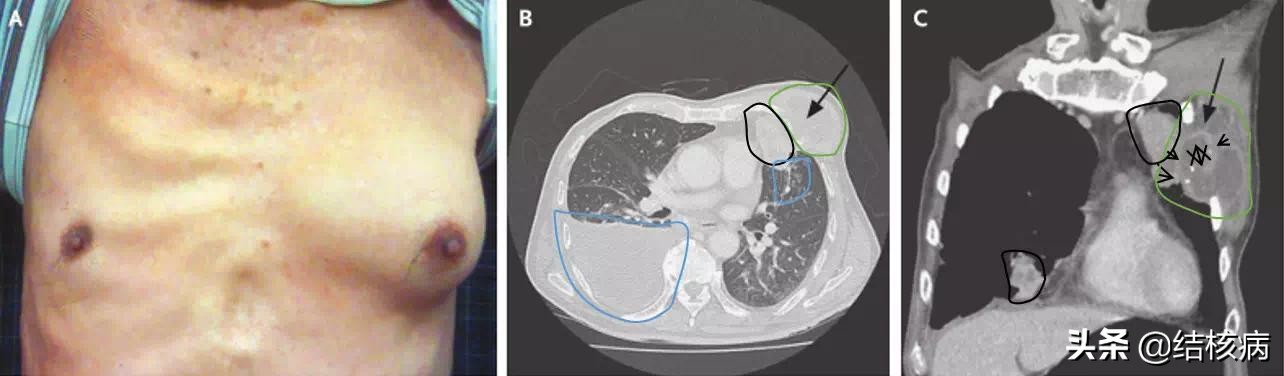

六、胸壁结核

胸壁结核是指胸壁软组织、肋骨、肋软骨及胸骨发生的结核病变,常继发于肺或胸膜结核,以青少年和年老体弱者多见。据有关资料报道,胸壁结核病人年龄最大71岁,最小13岁,胸壁结核同时患有肺结核、结核性胸膜炎者占47.3%;患有淋巴结核占21.4%;患泌尿生殖结核占16%;脊柱、四肢结核占12.8%;未发现有结核病的占2.5%。随着结核病化疗的进展,胸壁结核的患病率虽有下降,但胸壁结核仍为常见病。

结核感染使胸壁软组织发生干酪样坏死、化脓,形成结核性脓肿,病变为一慢性过程。结核菌主要经过下列途径侵入胸壁:①绝大部分经淋巴途径。肺结核、胸膜结核、胸椎结核、纵膈结核、腋窝淋巴结结核病灶内的结核菌经由淋巴管感染肋间淋巴结或胸骨旁淋巴结。组织呈干酪样坏死、化脓形成冷脓肿。脓肿破溃后,由于大量脓汁向周围压迫与灌注,而形成不规则的窦道。向肌层浅表溃破,与皮下形成隆起,甚至溃破到皮肤表面,造成经久不愈的慢性窦道。脓汁亦可穿透肋间肌,向内、外侵及。向内可在壁层胸膜外形成脓肿,向外可穿通至肋骨前方的软组织,形成哑铃状脓肿,甚至肋骨或胸骨感染骨质破坏。②肺和胸膜结核及颈部淋巴结核可直接波及肋间或胸壁软组织。③尚有少数患者为结核性脓胸手术时,如污染胸壁创面;或肋骨外伤;或结核菌经血循环进入肋骨或胸骨,引起结核性骨髓炎,进而形成骨膜下脓肿。